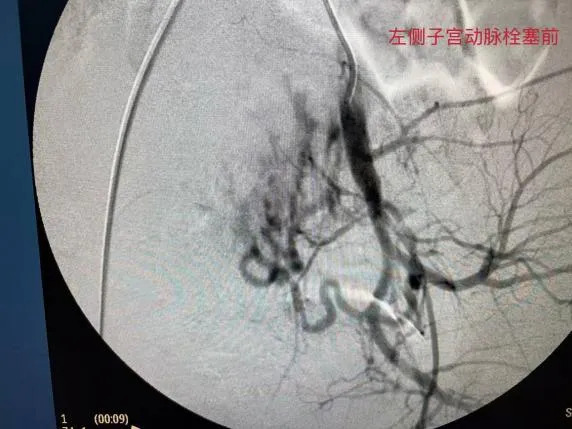

放射影像科主任胡达紧盯着屏幕,手中的导丝精细操作。他需要通过股动脉上一个针尖大小的穿刺点,将导管送到盆腔深处。造影剂注入的瞬间,屏幕上清晰地显示出正在大量出血的动静脉瘘口。

随后,胡达将栓塞剂精准地送入靶血管,迅速封堵这条失控的通道。出血瞬间停止,监护仪上的数字开始趋于稳定。